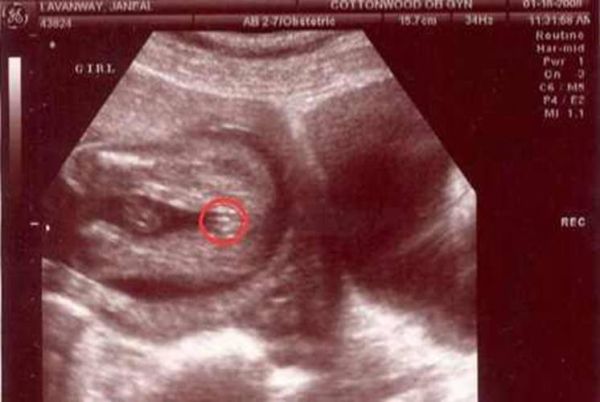

1. 看“三条线”还是“小突起”

传言:女宝大腿间是三条平行线(阴唇),男宝是一个小突起(阴茎)。 真相:误差极大。 • 女宝的阴唇在16周时仅毫米级,常被误判为脐带; • 男宝的阴茎若贴腹,看起来也像平坦皮肤。 临床统计:仅凭肉眼判断,准确率不足60%,和抛硬币差不多。